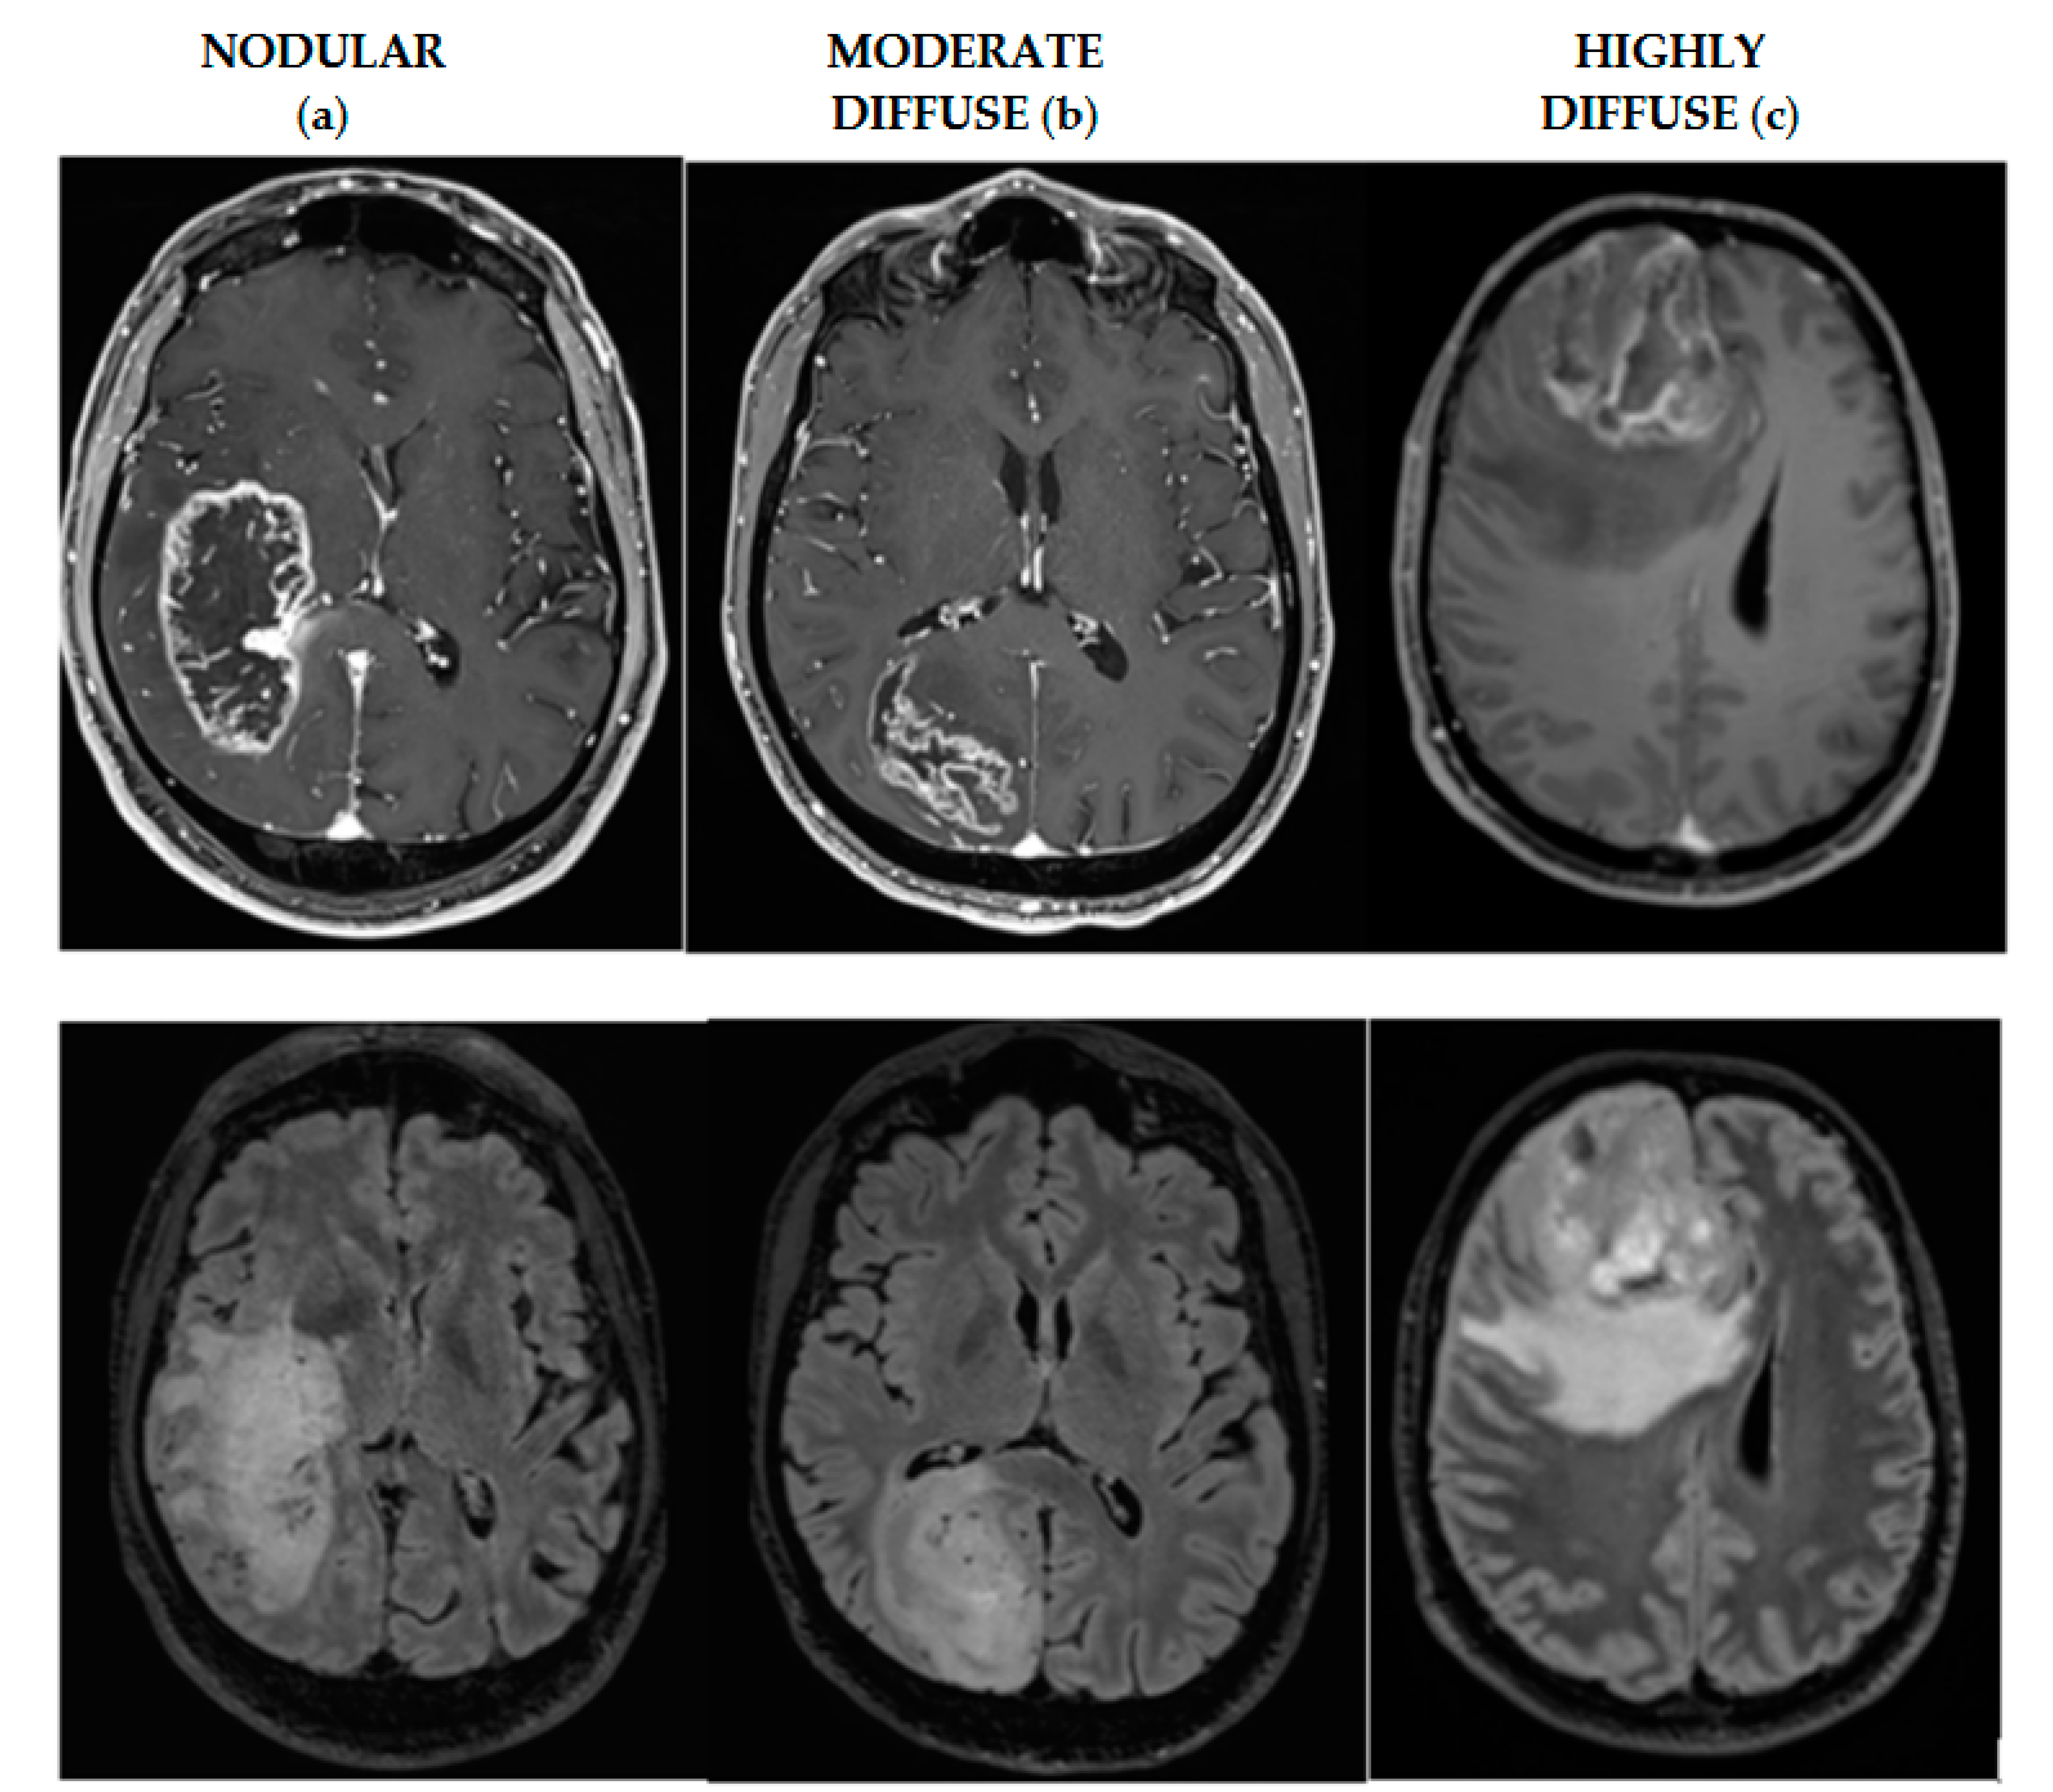

| Tumor invasiveness | |

| Highly diffuse | 20 (38.46%) |

| Moderate diffuse | 18 (34.61%) |

| Nodular | 14 (26.93%) |